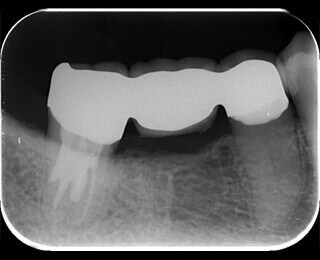

症例2 レントゲンで見てもしっかり治療が終わっているのにまだ疼く

マイクロスコープで小さい神経を見落とさない。

歯の神経は非常に細いため肉眼ではたびたび神経を見落としてしまうことがあります。

(この症例ではMB2という細い神経を見つけることができました)

7

矢印の部分にわずかに小さい穴が見えます。

2つ神経があるように見えます。

10

真ん中にもう一つ隠れていました。